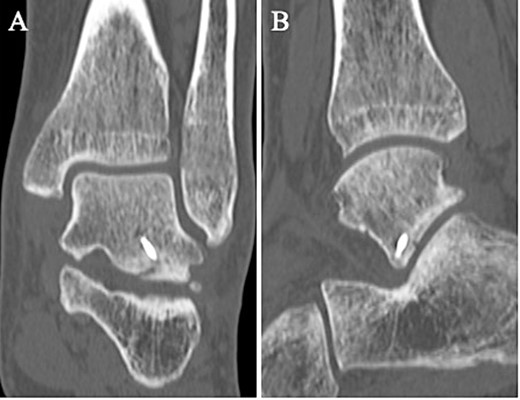

Postoperatively, a non-weightbearing short leg splint was postoperatively applied for 2 weeks. Active and passive range of motion exercises of the ankle were permitted at 2 weeks postoperatively. Partial-weightbearing was allowed at 4 weeks postoperatively, and full-weightbearing at 6 weeks postoperatively. The patient was allowed to jog 8 weeks after surgery. After confirming that bone union was obtained on non-contrast CT (Fig. 5) and tenderness on the lateral side of the ankle had resolved, the patient was allowed to return to his original sport at 12 weeks postoperatively. Two years after surgery, the patient remained a competitive basketball player with no symptoms. Additionally, the AOFAS score had improved to 100 points.

A non-contrast CT taken at 12 weeks postoperatively showed bone union in the coronal (A) and sagittal (B) views.